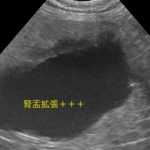

超音波検査で左右の腎盂が著しく拡張していたので、そのまま、無麻酔CT検査を行い左右の尿管結石による左右の腎盂拡張が確定されました。直ちに経皮的腎盂穿刺により、腎後性高窒素症、代謝性アシドーシス、高カリウムの補正を行いました。来院から約36時間で高カリウムが消失し、血液データが改善してきたことから、両側同時にマイクロサージェリーで尿管切開により結石摘除を行いました。術後は結石が閉塞していた影響で尿管炎が顕著になるため、尿管狭窄を予防するために、尿管内に一時的ステント留置を行いました。数週間後に再び麻酔下でステント抜去を行います。また、症例によって腎下方移動尿管膀胱吻合術に移行する場合もあります。徐々に腎数値も良化し、尿も沢山排泄されているようで一安心です。